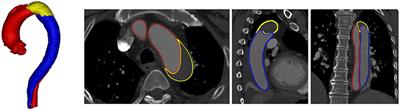

Quantifying Patient-Specific in vivo Coronary Plaque Material Properties for Accurate Stress/Strain Calculations: An IVUS-Based Multi-Patient Study